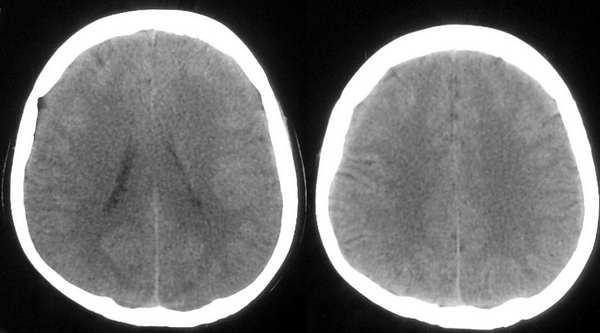

患者,女,32岁,时有头晕,无恶心呕吐。

这个病例为正常的头部ct表现,只是由于摆位不正而造成了诸多疑问,所以在工作中要注意摆位问题。

我认为是正常的颅脑影像。左侧颞顶叶脑组织示略高密度结构是近外侧裂区的正常皮质结构,不是灰质移位。由于摆的位置不正,左侧的脑组织较右侧的低一个层面。